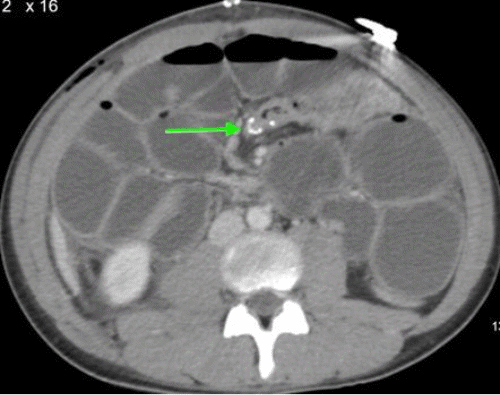

Contrast-enhanced CT scan of the abdomen and pelvis revealed findings consistent with mechanical obstruction. A transition point abutting the abdominal wall at the prior projectile injury site was noted proximal to the ileocolic anastomosis (Figure 3). A small bowel follow-through demonstrated small amounts of contrast in the distal small bowel loops at an 8-hour delay, indicating possible incomplete obstruction (Figure 4). Following discussion with the patient and guardian, a decision was made to perform a re-exploratory laparotomy.

(C) Axial view  of the ileocolic anastomosis (green arrow)

(D) Sagittal view of the ileocolic anastomosis (green arrow)